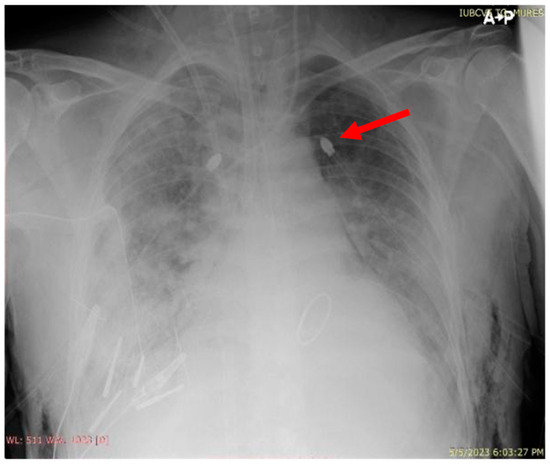

| Day 1 | The patient developed a left pneumothorax, confirmed by thoracic X-ray, worsening respiratory parameters, therefore requiring the insertion of a drainage tube. A thoracic X-ray after drainage confirmed the correct positioning of the tube and the complete expansion of the left lung. | |

| Day 3 | The endotracheal cannula was changed to a double-lumen right-sided cannula, and the patient was placed on two ventilators operating independently. The parameters were adjusted based on the patient’s progress and needs. | |